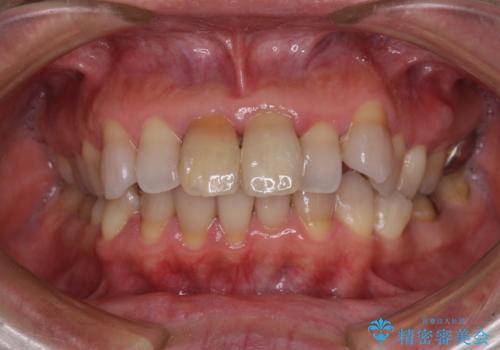

- 変色した前歯2本を気にして来院された患者様です。

右側の前歯は根管治療を行い、その後2本とも歯質に近い素材の土台を植立してオールセラミッククラウンにて補綴することとしました。